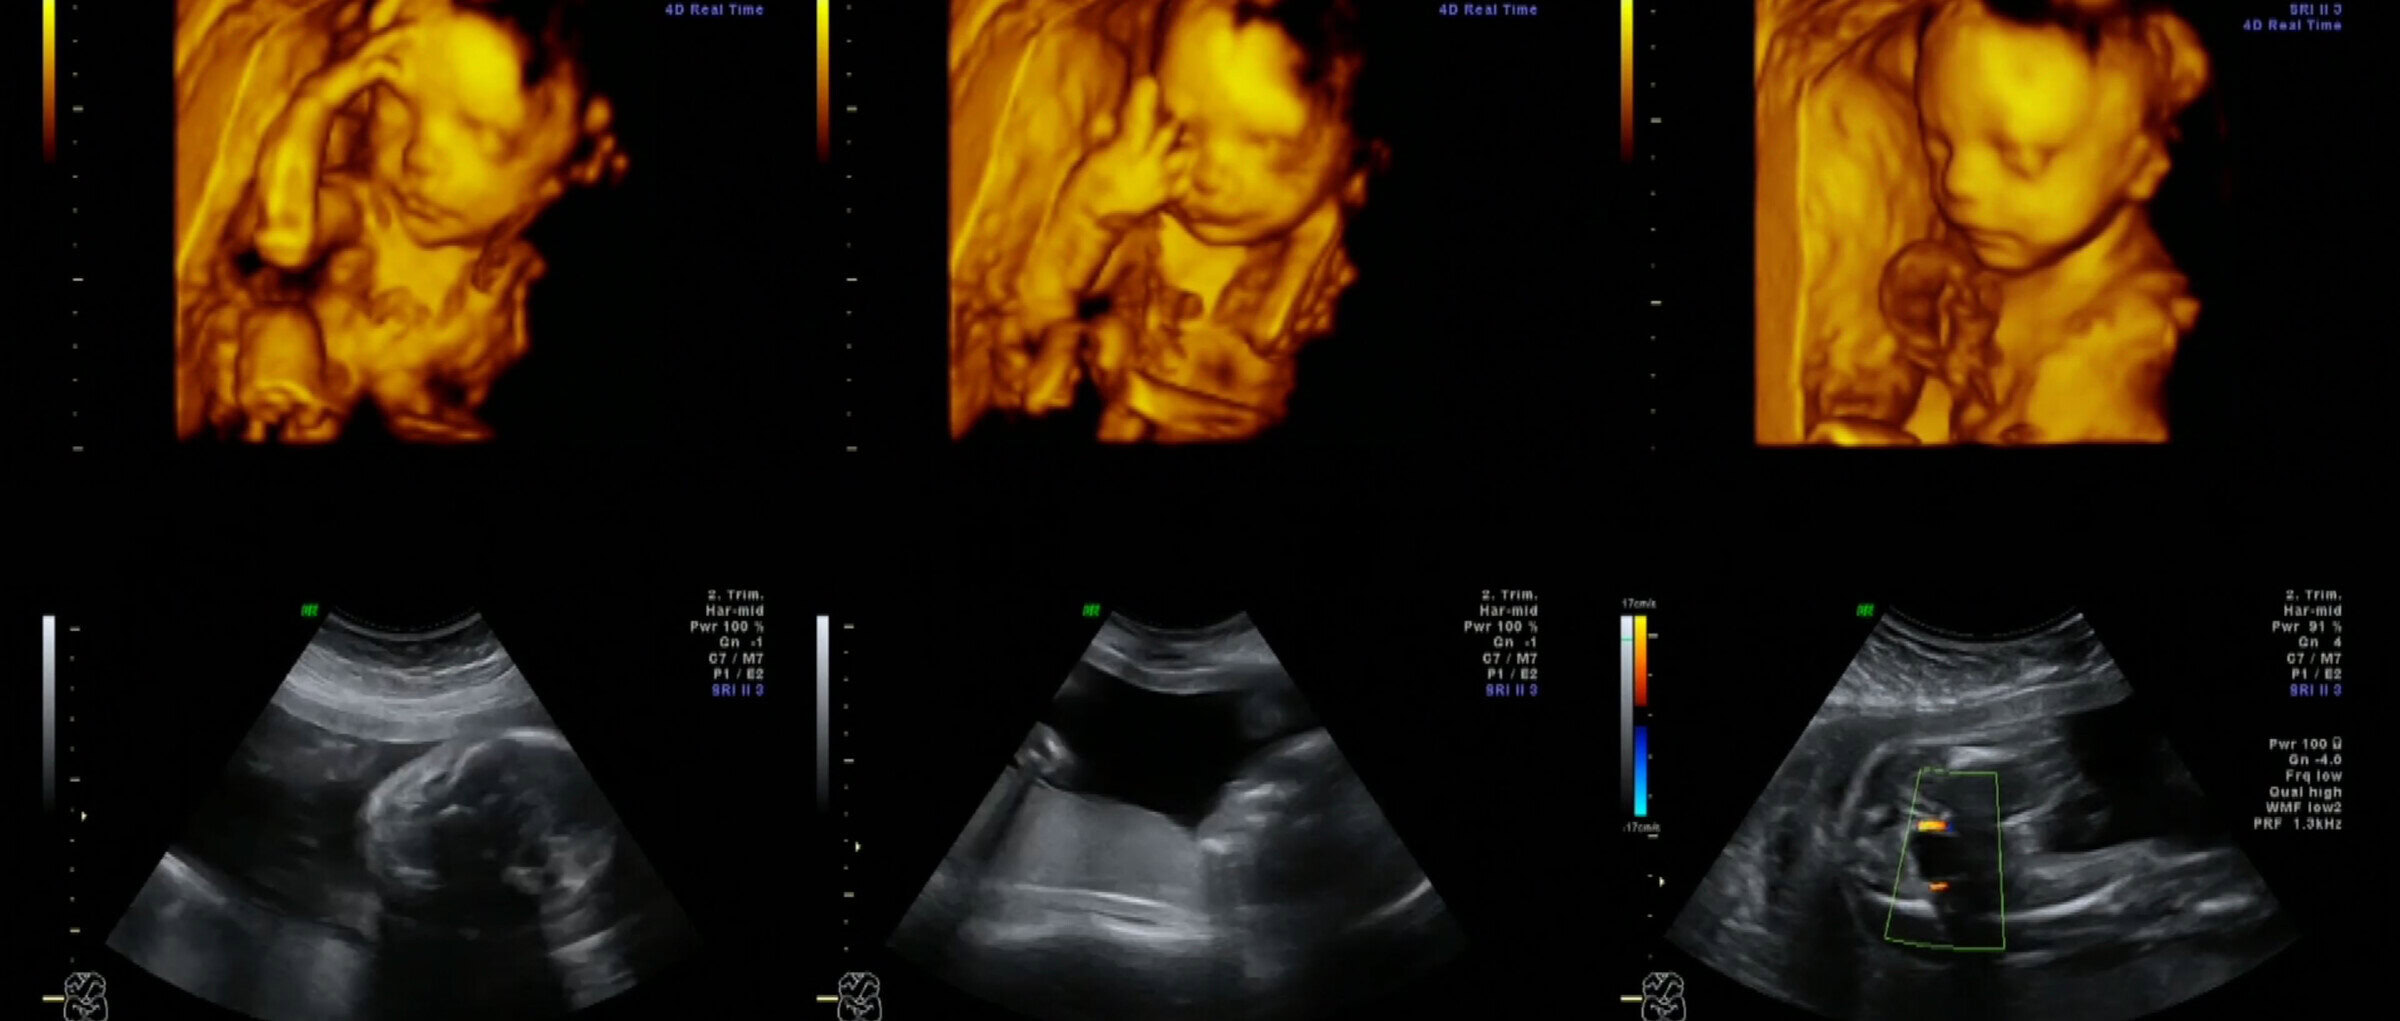

Through inaudible sound waves, Ultrasounds deliver high-quality moveable images in real time without the use of radiation. They are commonly used in obstetrics, small parts, abdominal and pelvic, and musculoskeletal and vascular imaging. There is no use of radiation, making ultrasounds exceptionally safe .

You will find the latest in Ultrasound technology in South East Queensland available at Breast Health Imaging.